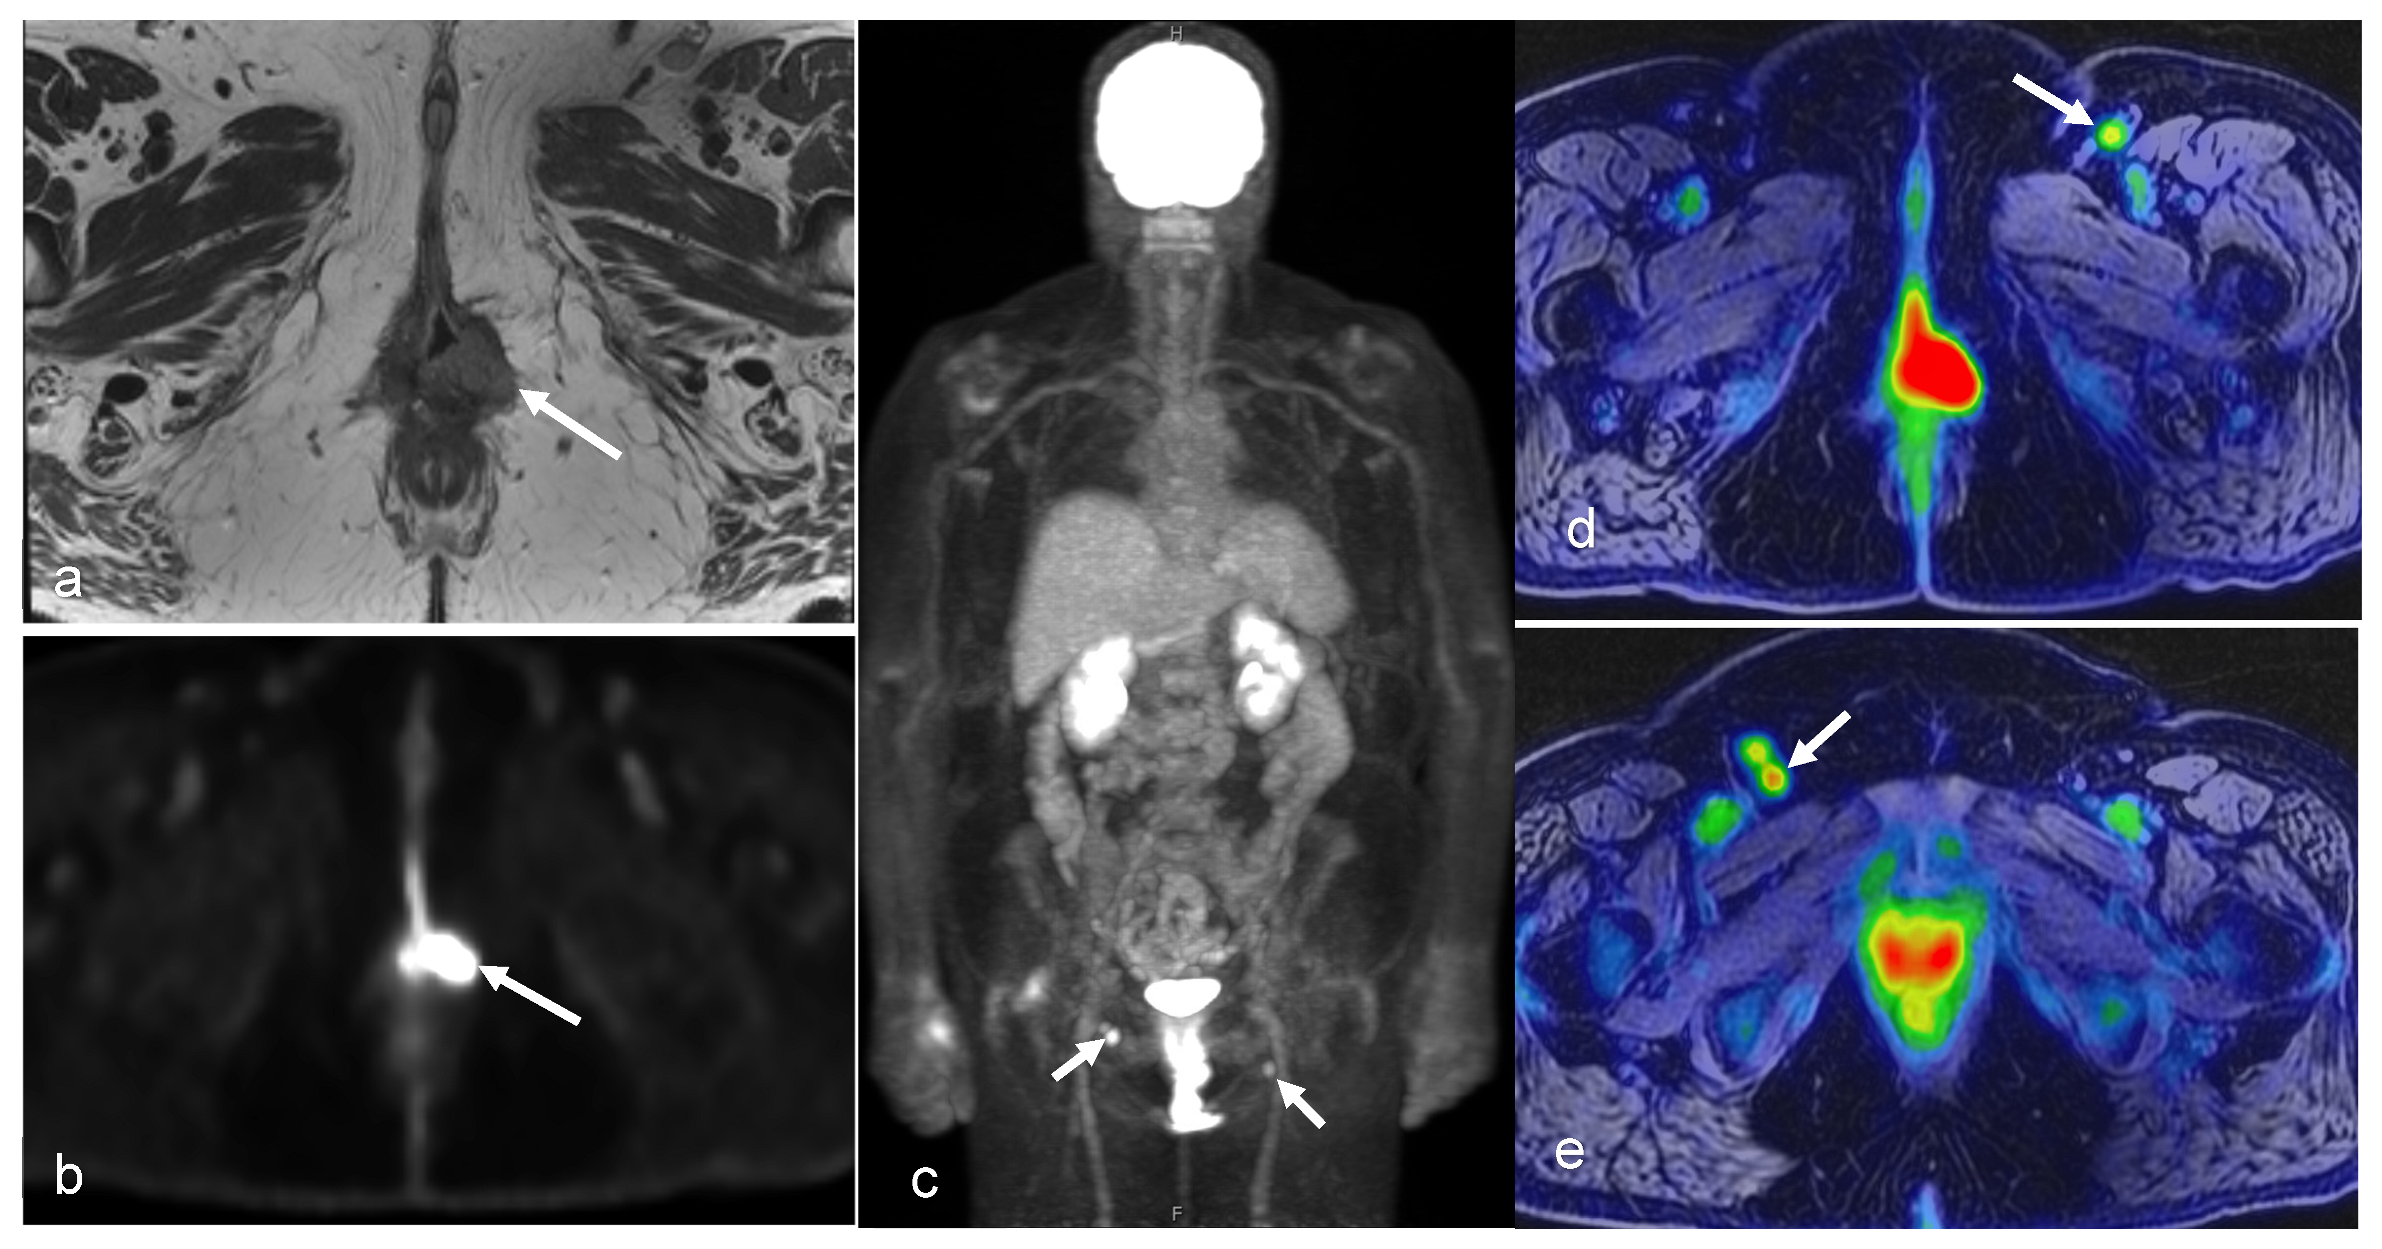

3.4. Vaginal and Vulvar Cancers

- Chow, L.; Tsui, B.Q.; Bahrami, S.; Masamed, R.; Memarzadeh, S.; Raman, S.S.; Patel, M.K. Gynecologic tumor board: A radiologist’s guide to vulvar and vaginal malignancies. Abdom. Radiol. 2021, 46, 5669–5686. [Google Scholar] [CrossRef] [PubMed]

- Cohn, D.E.; Dehdashti, F.; Gibb, R.K.; Mutch, D.G.; Rader, J.S.; Siegel, B.A.; Herzog, T.J. Prospective evaluation of positron emission tomography for the detection of groin node metastases from vulvar cancer. Gynecol. Oncol. 2002, 85, 179–184. [Google Scholar] [CrossRef]

- McGettigan, M.; Zulfiqar, M.; Shetty, A.S. Imaging of Vaginal and Vulvar Malignancy. Radiol. Clin. N. Am. 2023, 61, 651–670. [Google Scholar] [CrossRef]

- Expert Panel on GYN and OB Imaging; Kilcoyne, A.; Gottumukkala, R.V.; Kang, S.K.; Akin, E.A.; Hauck, C.; Hindman, N.M.; Huang, C.; Khanna, N.; Paspulati, R.; et al. ACR Appropriateness Criteria(R) Staging and Follow-up of Primary Vaginal Cancer. J. Am. Coll. Radiol. 2021, 18, S442–S455. [Google Scholar] [CrossRef]

- Preti, M.; Bucchi, L.; Micheletti, L.; Privitera, S.; Corazza, M.; Cosma, S.; Gallio, N.; Borghi, A.; Bevilacqua, F.; Benedetto, C. Four-decade trends in lymph node status of patients with vulvar squamous cell carcinoma in northern Italy. Sci. Rep. 2021, 11, 5661. [Google Scholar] [CrossRef] [PubMed]

- Rufini, V.; Garganese, G.; Ieria, F.P.; Pasciuto, T.; Fragomeni, S.M.; Gui, B.; Florit, A.; Inzani, F.; Zannoni, G.F.; Scambia, G.; et al. Diagnostic performance of preoperative [18F]FDG-PET/CT for lymph node staging in vulvar cancer: A large single-centre study. Eur. J. Nucl. Med. Mol. Imaging 2021, 48, 3303–3314. [Google Scholar] [CrossRef] [PubMed]

| Vaginal/Vulvar | Benefit(s) | Helpful in determining disease extent and nodal/metastatic involvement [42] Useful for identifying distant metastases, including pulmonary and bony metastases in vulvar cancer [42] | The modality of choice for locoregional assessment, detection of primary and metastatic cancer, and treatment response The most sensitive modality for detecting pelvic lymph node involvement [42] | Useful for radiation therapy planning [43], assessing response to neoadjuvant chemotherapy and guide patient management Evaluation of nodal and distant metastatic involvement in staging of recurrent vaginal cancer [42] | Helpful in for detecting vulvar cancer recurrences and distant metastases [42] |

| Pitfall(s) | Difficulty in assessing lymph node involvement, especially in small or micro-metastatic nodes Inability to determine local tumor staging due to low soft tissue contrast [42] | Limited value in detecting lymph node metastases ≤ 5 mm and necrotic lymph nodes False-positive (e.g., inflammatory lymph node) [23] |